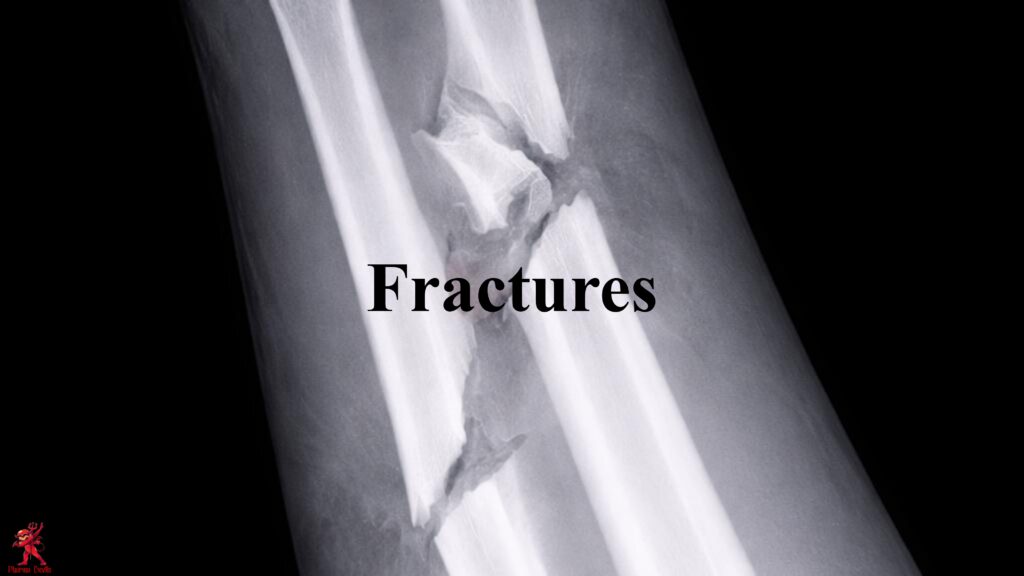

Pictorial SOP on First Aid